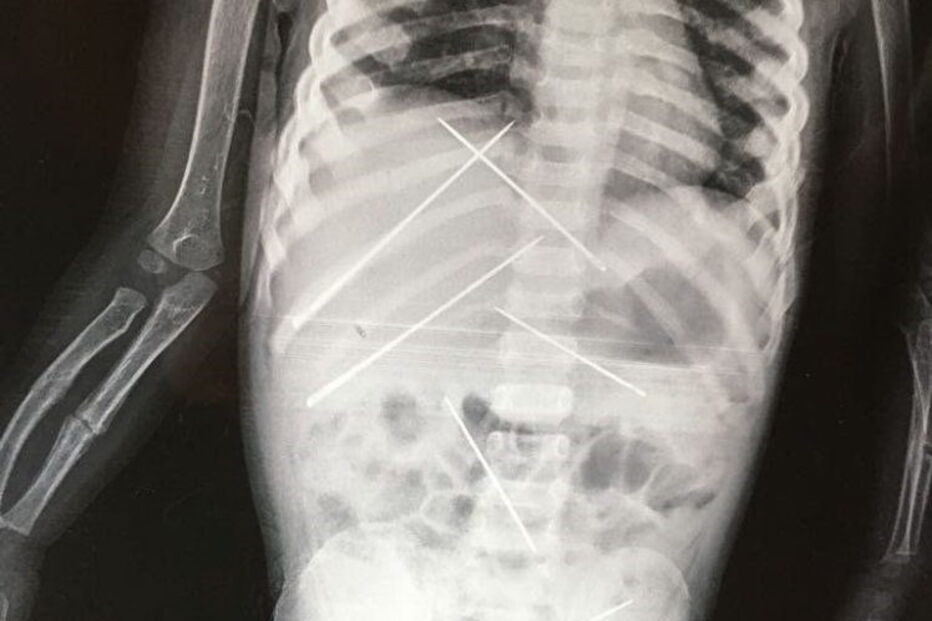

A criança de três anos tinha mais de sete agulhas no abdómen.

Um homem é acusado de fazer 'magia negra' a uma criança perfurando-a com agulhas, em Bankura, na Índia. Foram descobertas mais de sete agulhas no abdómen da vítima.

A criança foi assistida no Hospital SSKM, em Kolkata. Os médicos descobriram várias agulhas inseridas no corpo da vítima, que tinha também um braço partido.

Quando os médicos se aperceberam da gravidade do caso, decidiram não retirar as agulhas. Mantiveram-na durante dois dias sob observação, para decidir o que haveriam de fazer.

Foi operada e os médicos continuam a tentar estabiliza-la e ajudá-la a ultrapassar o trauma. De acordo com os médicos, a mãe da criança disse-lhes que as agulhas estavam dentro do seu corpo há mais de 15 dias.